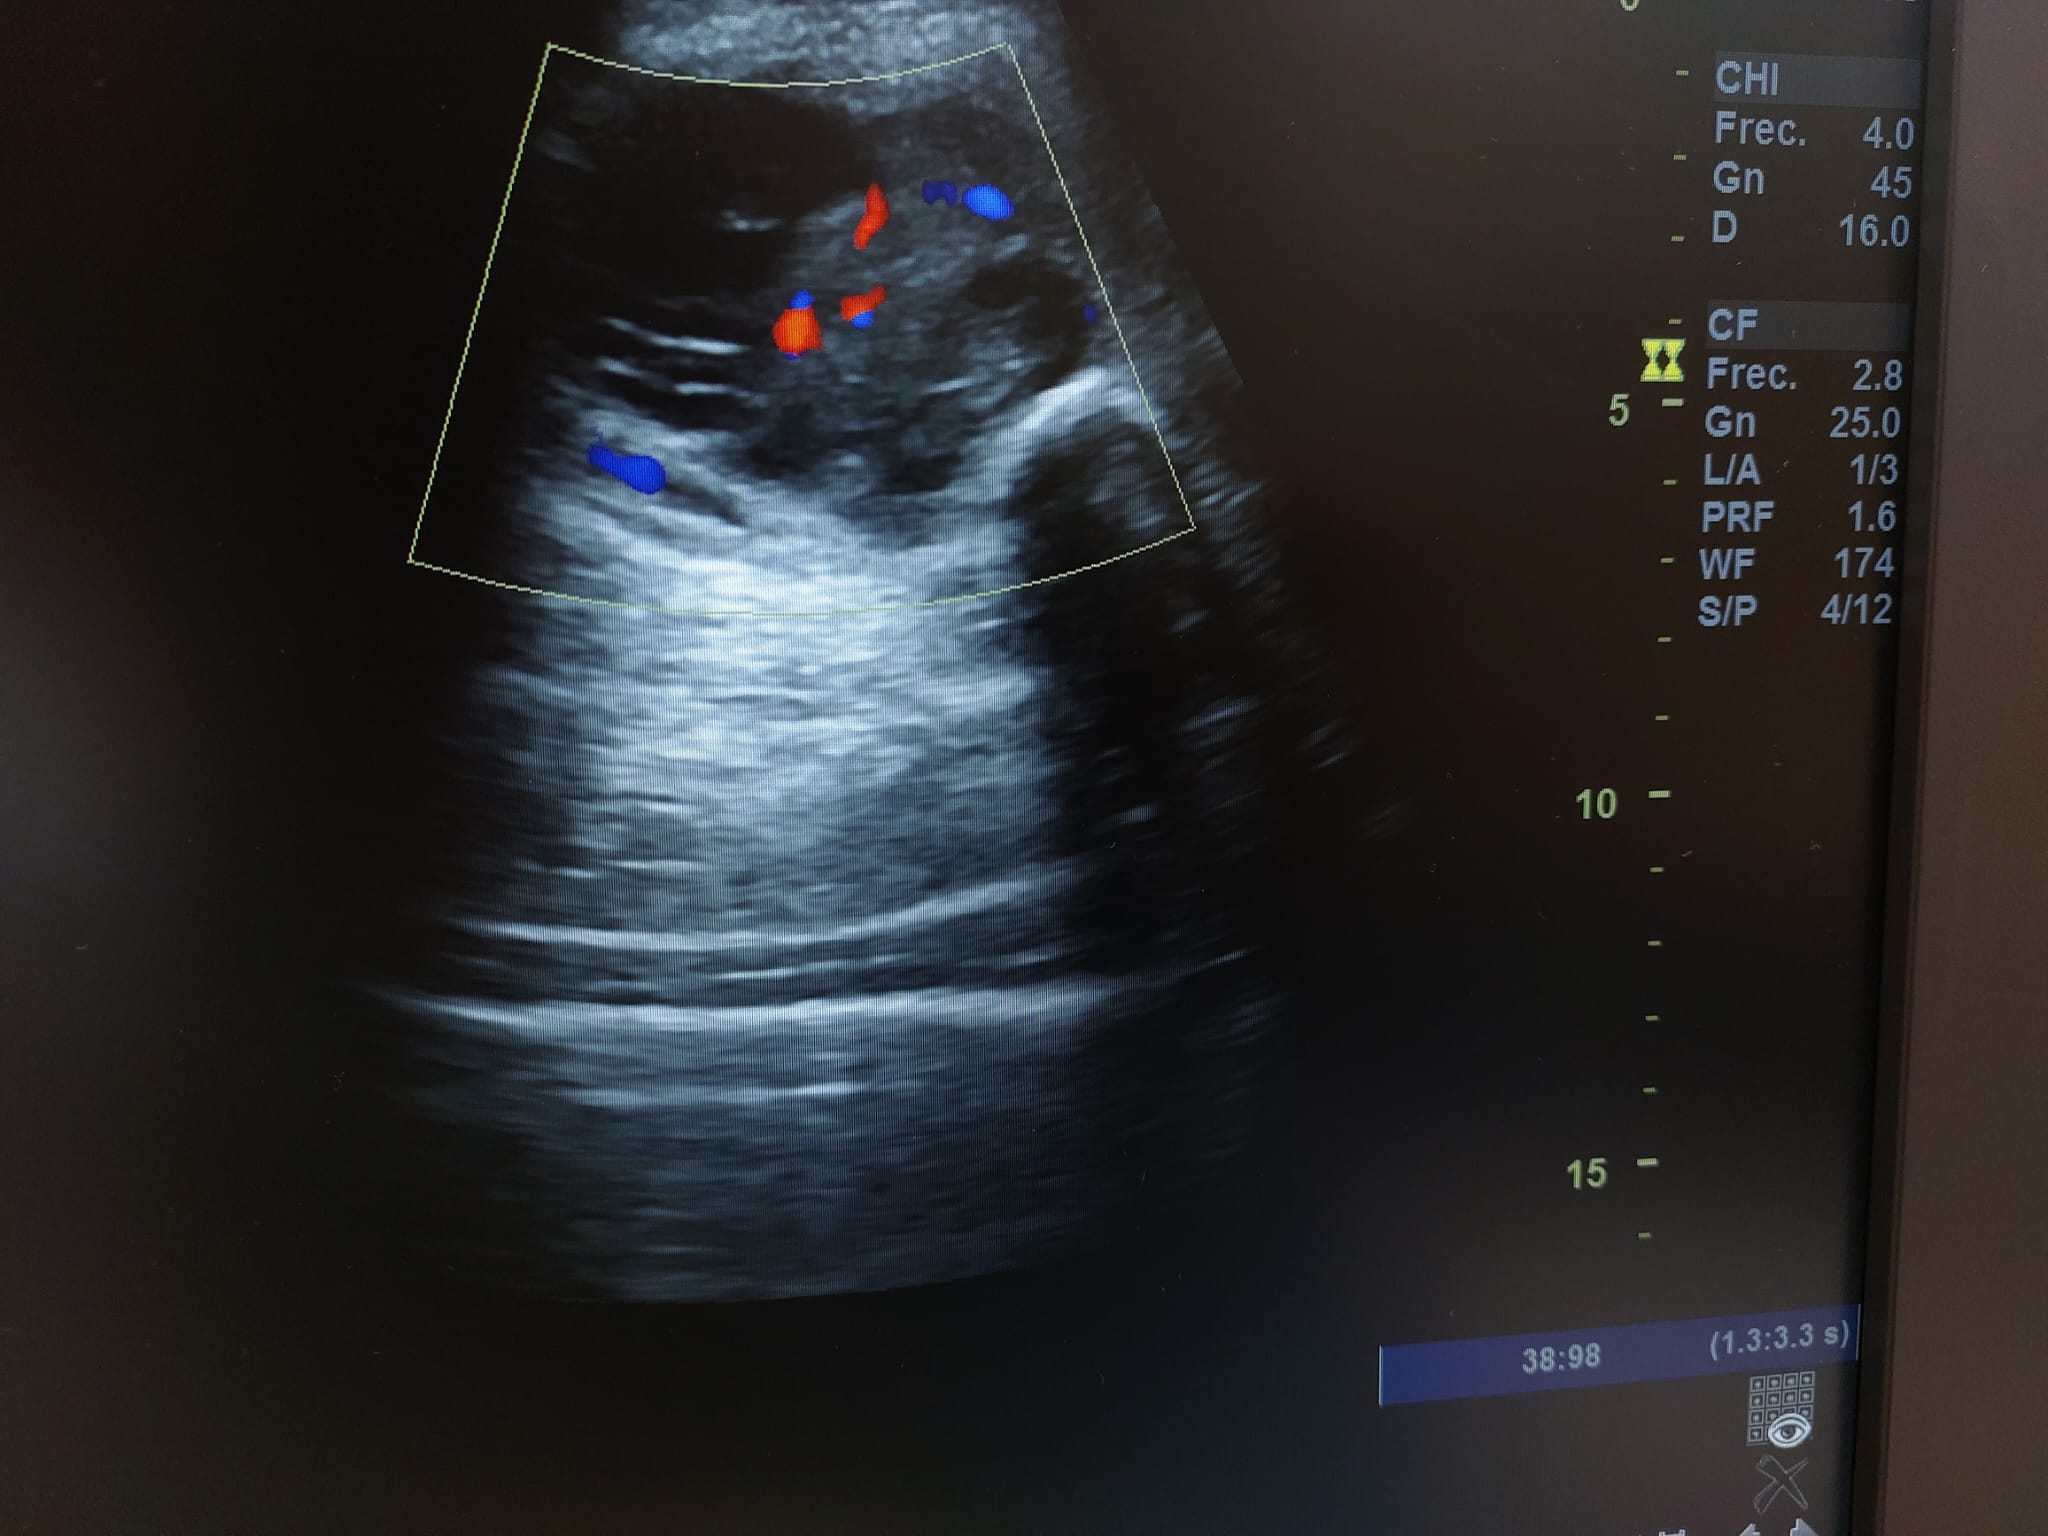

Descripción de los hallazgos ecográficos y las imágenes más relevantes para la resolución del caso

Se realiza ecografía observando colección anecoica a nivel muscular compatible con hematoma organizado, de aproximadamente 7 x 4 cm.

En el seguimiento se observa evolución tórpida sin mejoría clínica y en la ecografía de control se observa aumento notable de tamaño respecto al previo, estructura heterogénea de imagen anecoica con septos internos. Se aprecia edema intramuscular perilesional y captación al activar el Doppler. Se plantea la posibilidad de un hematoma sobreinfectado o, debido a su importante crecimiento, una probable etiología neoplásica. Tras hallazgos descritos en consulta, COT solicita de forma urgente la realización de RNM y biopsia de la lesión. Posteriormente, el resultado de las pruebas complementarias confirman diagnóstico de sarcoma histiocítico.